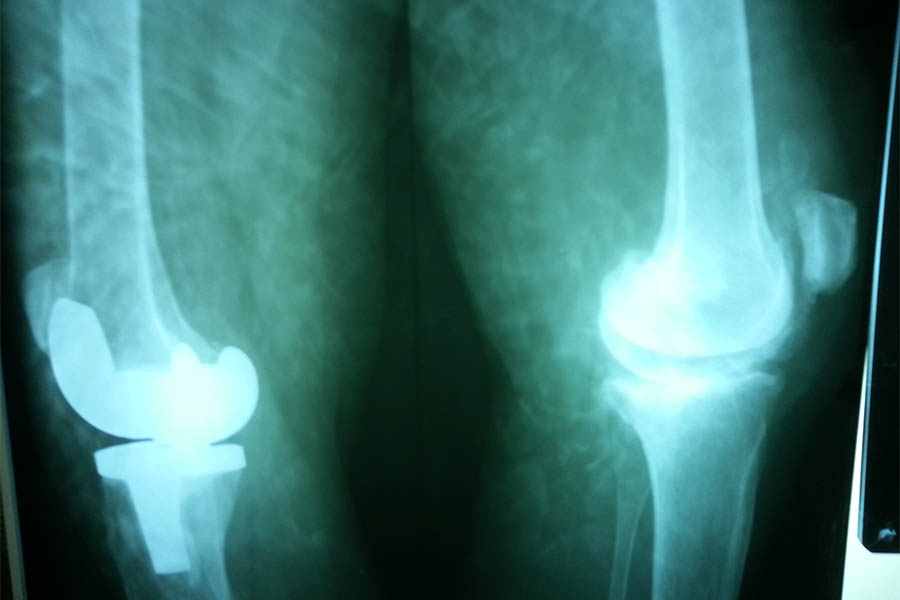

Total Knee Replacement

Case 1